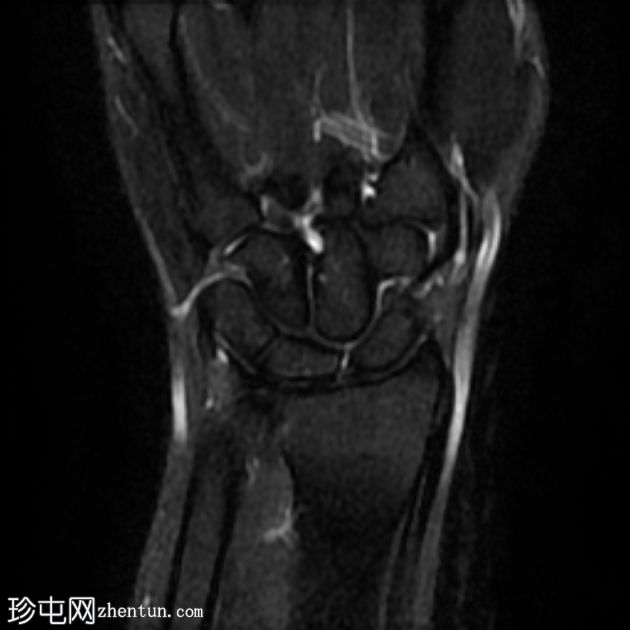

MRI

冠状位

T2加权像

腕背多房性腱鞘囊肿(轴位、矢状位和冠状位图像均可见),位于伸肌腱下方的腕背关节囊内,提示为腕背腱鞘囊肿。

该病例展现了腕背腱鞘囊肿的典型

影像

学表现和位置。